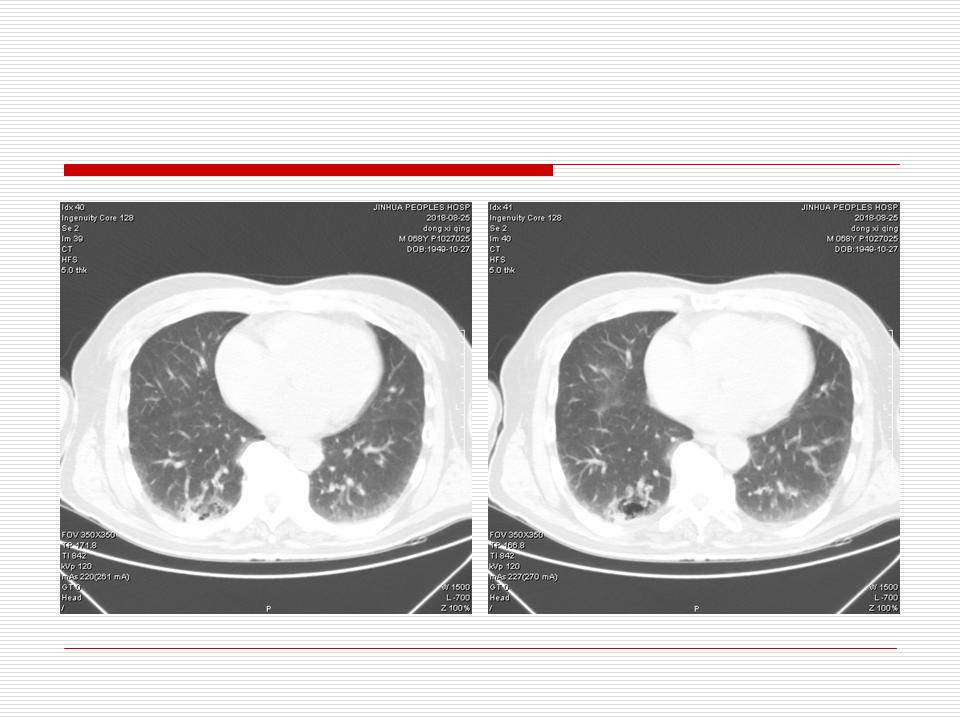

肺部阴影永恒且最重需要鉴别的是:到底是炎症还是肿瘤?但临床的病例中的影像表现难以界定或有些肿瘤特征,同时又有些炎症特点是非常常见的情况。作为临床医生我们怎么去总结分析,并找到之所以是炎症或之所以是肿瘤的细微差别或特点非常重要,也非常有用。2019.12.7浙江省2019年胸心外科学学术年会在宁波召开时,我的临床病例分析与经验总结<那些像肺癌的炎症与像炎症的肺癌>获得在大会交流的机会,以下为该PPT的内容,与你分享,希望对同道有益,有借鉴与启迪。若有探讨与进一不完善的建议,欢迎文末留言讨论: